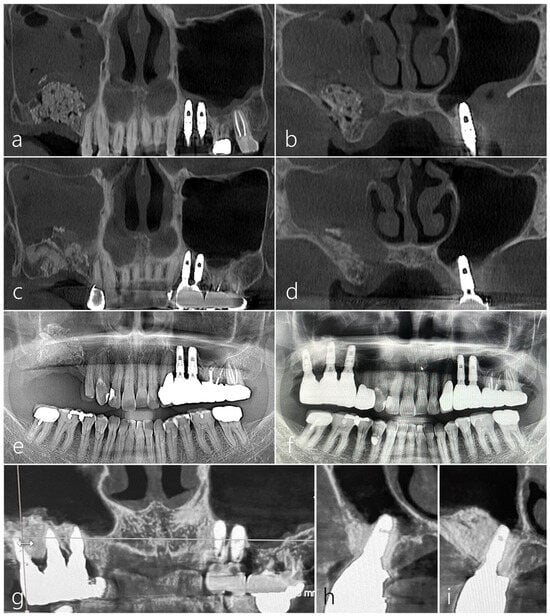

2.1. Case 1